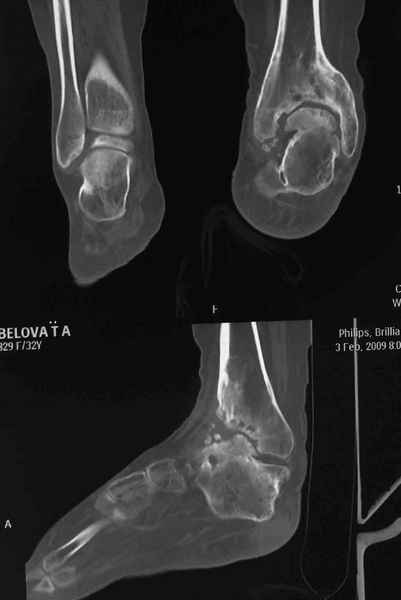

Пациентка Б. получила травму 2001 году в результате падения с высоты. За это время дважды выполнялись неудачные попытки артродезирования голеностопного сустава. Больная перед нами поставила одну задачу - восстановить опороспосонбность левой нижней конечности и только. Принято решение выполнить кейдж-артродезирование левого голеностопного сустава блокируемым интрамедуллярным гвоздем с установкой сетчатого опорного трансплантата, костной аутопластикой плюс Chronos. С целью профилактики рецидива деформации выполнили ахиллотомию (считаем, что неудачи предшествующих операций связаны с варусной тягой ахиллова сухожилия в ррезцльтате неправильно сросшегося перелома пяточной кости). На сегодняшний день - два месяца с момента операции. Пациентка перемещается в циркулярной повязке с полной нагрузкой на больную ногу.